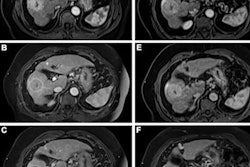

Patients were randomized to undergo two MRIs with gadopiclenol and then gadobutrol (or vice versa) over a 14-day interval. Three readers assessed the clarity of lesion visualization by such measures as the delineation of the lesion border, its internal morphology, and contrast enhancement, ranking these measures on a four-point scale (with 1 equal to poor and four equal to excellent). Wolansky and colleagues tracked the percentage of enhancement, lesion-to-background ratio, and contrast-to-noise ratio, and any adverse events that occurred within a day after the second MRI exam.

The study showed that gadopiclenol performed on par with gadobutrol in all of the visualization criteria (p < 0.0001). But it actually outperformed gadobutrol when it came to the two measures of the percentage of enhancement and lesion-to-background ratio (p < 0.0001).